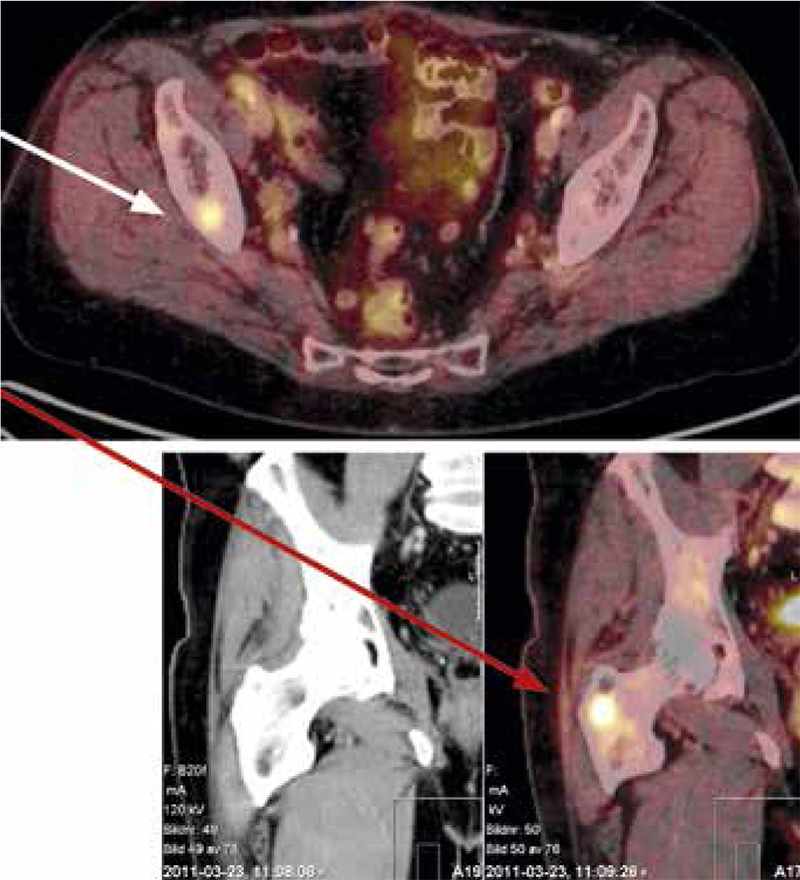

Ytterligare diagnostik behövdes för 21 av de 58 patienterna med lungcancer, vanligen för att bekräfta cancerdiagnosen i tveksamt operabla fall eller där riktad strålbehandling (i regel med transtorakal punktion) övervägdes (nio fall) eller för att utesluta eller konfirmera spridd sjukdom. Sensitiviteten för cancer var hög vid PET/DT. Endast en av de 63 maligniteterna bedömdes vara negativ (Tabell I, Figur 1). Spridd sjukdom (stadium 4) kunde påvisas hos 17 patienter.

Den vanligaste metastaslokalen var skelettet, där flertalet patienter saknade lokala symtom (Figur 2 och 3). Engagemang av regionala lymf­körtlar påvisades också i många fall. Tre fall av tidigare ej känd synkron tumör påvisades: bröstcancer, prostatacancer respektive rektalcancer. Falskt positiva fynd förekom också vid t ex infektioner.

Figur 1. Kvinna född 1963. PET/DT bedömd som sannolikt benign. Transtorakal lungpunktion av tumör (pilen) visade adenokarcinom och torakotomi dessutom flera positiva N1-körtlar. DT vänster bild, PET/DT höger bild.

Figur 3. Ockult skelettmetastas vid rutinmässig PET/DT-undersökning.